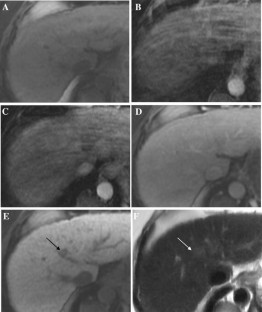

Fig. 4